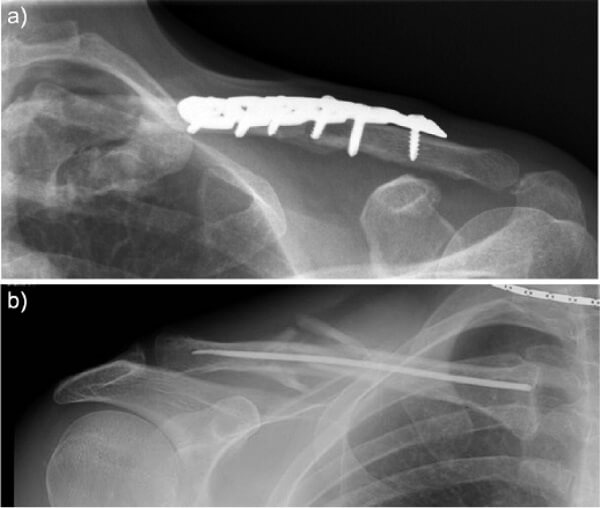

Phẫu thuật gồm có 2 kỹ thuật là: Sử dụng đinh Kirschner và phẫu thuật kết hợp xương với nẹp vít.

Ưu điểm của phẫu thuật là giúp người bệnh nhanh chóng liền xương nhưng kèm theo đó cũng có những rủi ro như nguy cơ bị viêm xương, nhiễm trùng tại vết mổ, gãy nẹp, chồi đinh, có sẹo mổ ở vùng trước của xương đòn khiến ảnh hưởng tới thẩm mỹ.

Tiếp đó các bác sĩ sẽ tiến hành chụp X-quang để xác định chính xác đường gãy, vị trí, sự di lệch của xương quai xanh. Chụp CT cắt lớp cũng có thể được thực hiện để xác định kiểu gãy, di lệch. Ngoài ra, nếu cần phải mổ thì sẽ thực hiện các xét nghiệm cũng như cận lâm sàng trước mổ.